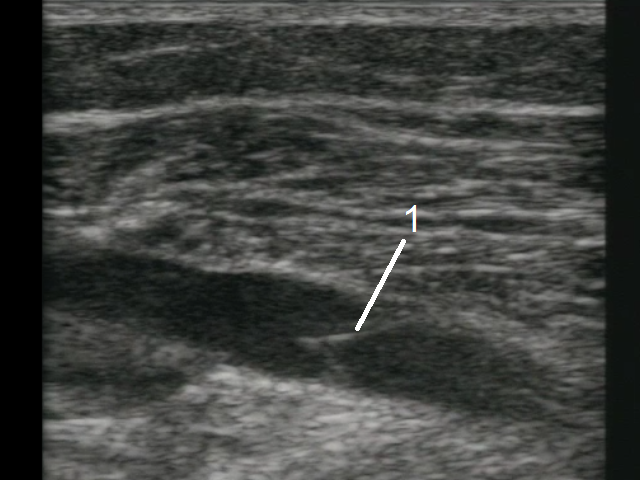

深部静脈血栓症(DVT)弁画像

弁